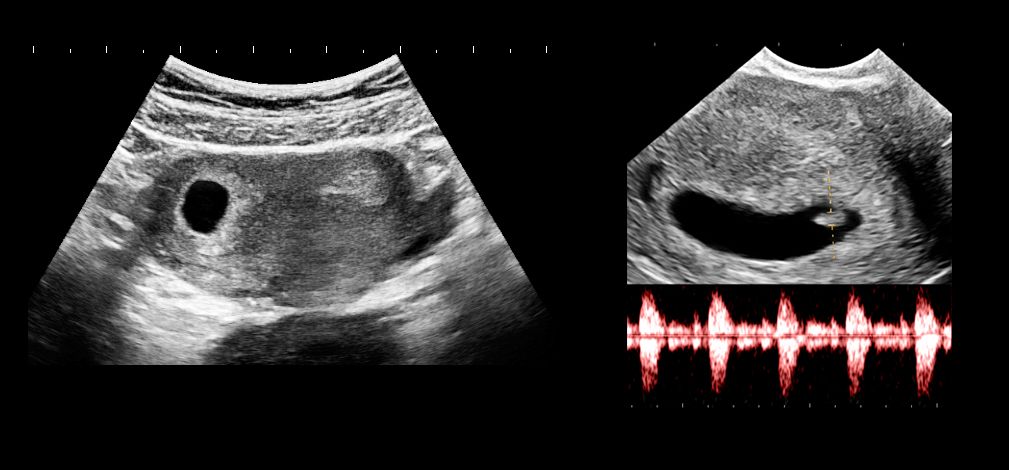

Ultrasounds repeated because of incomplete visualization of the fetus and detection of fetal abnormalities.